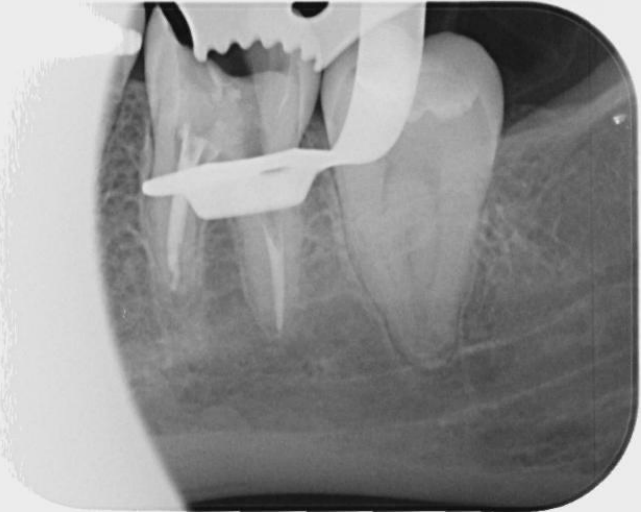

To assess the extent of the fracture and plan for removal, we obtained periapical radiographs and a cone-beam computed tomography (CBCT) scan. The imaging revealed the fractured NiTi instrument lodged deep within the canal system, complicating its retrieval due to its position approximately 8 mm beyond the apical foramen.

Fig 1, Fig 2, Fig 3, Fig 4, Fig 5, Fig 6, Fig 7

Figure 1

Figure 2